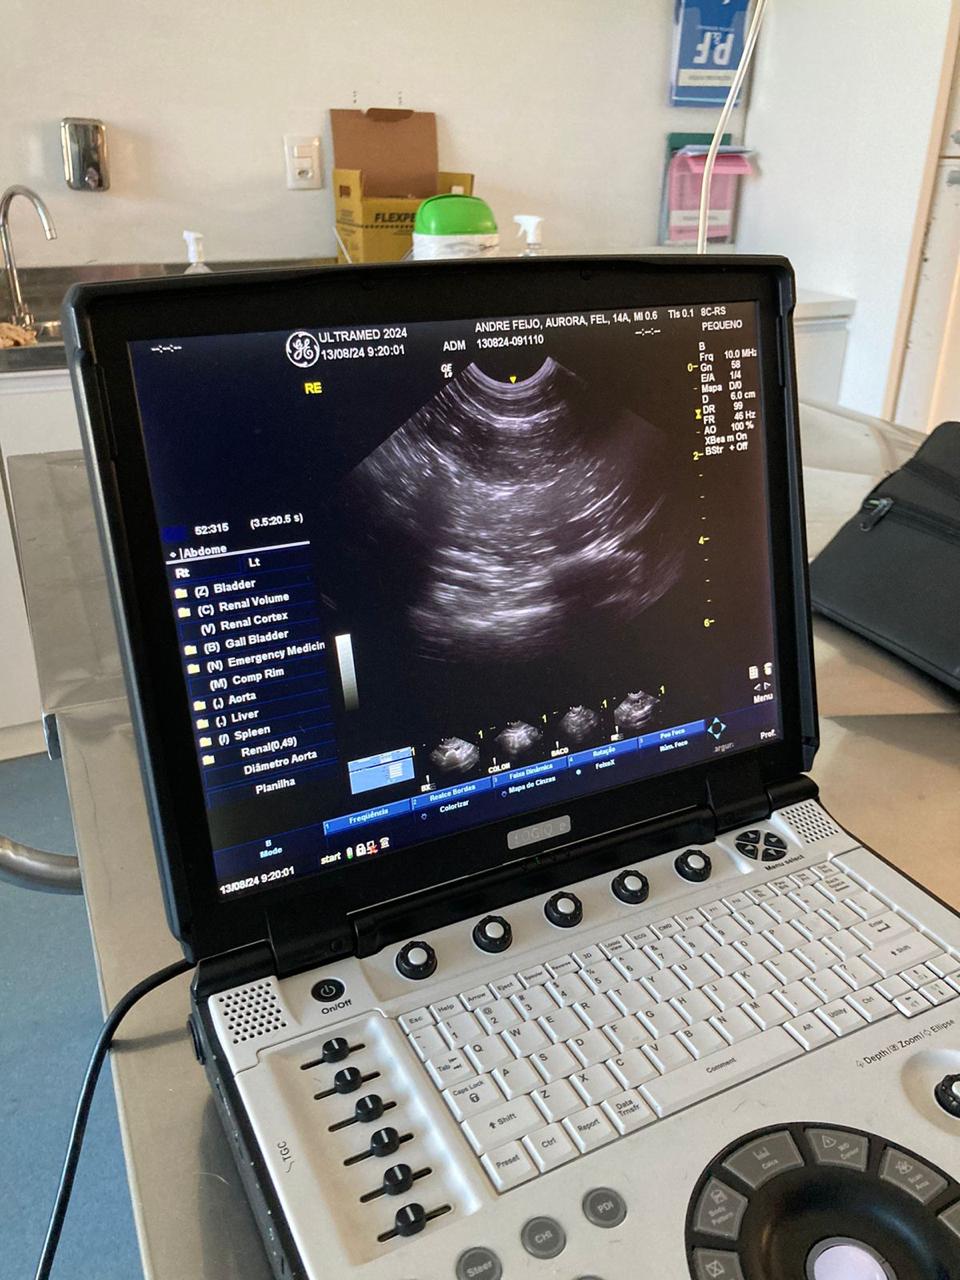

O ultrassom abdominal veterinário é um procedimento essencial para diagnósticos precisos e eficazes em animais.

Com este exame, é possível visualizar em tempo real órgãos internos, identificar possíveis doenças, monitorar a gestação, além de auxiliar no planejamento do tratamento veterinário.

A ultrassonografia abdominal é fundamental para identificar diversas condições de saúde, como tumores, doenças hepáticas, renais, entre outras.

Com imagens detalhadas e de alta qualidade, nossos especialistas conseguem realizar diagnósticos precisos e iniciar o tratamento adequado de forma rápida e eficaz.